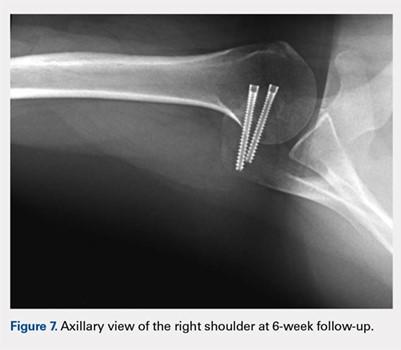

At her second visit (6 weeks), she was completely pain free. Clinical examination showed no tenderness at the acromion, healed incisions, and pain-free passive ROM. Radiographs demonstrated early evidence of consolidation and no sign of fixation failure (Figures 6-8). Her Single Assessment Numeric Evaluation (SANE) score was 85%, and her Simple Shoulder Test (SST) score was 3/12. She was permitted to discontinue the sling, to begin using the arm actively at the side, and progress with unloaded use above shoulder height over the next 6 weeks.